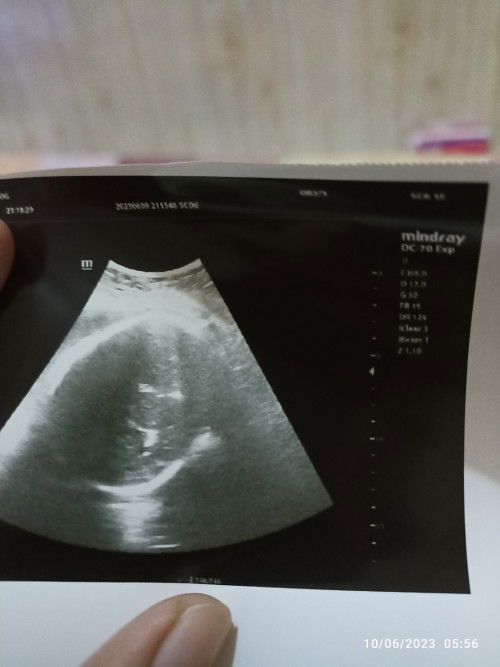

Air ketuban keruh dan sudah mulai berkurang. Hpl USG 5 Juni hpl hpht 21 juni

Bunda bunda mau tanya semalem saya Cek USG info dokter nya air ketuban sudah keruh dan mulai berkurang karena hpl USG sudah lewat 4 hari .. Kalau menurut hpht sya masih di 38week .. Sudah 3 hari ini mengalami keputihan saat bangun tidur, maaf sedikit kental dan lengket tp tidak berbau.. Sudah mulai sering kopal (kontraksi palsu) tp stelah saya istirahat ilang kembali. Menurut bunda sya coba cek lagi di dokter lain untuk memastikan benar air ketubanya keruh atau gmna yaa.. ?? Jujur jadi kepikiran banget krna info dokternya sperti itu...🥲 #seriusnanya #bantusharing #pleasehelp #Second_Baby